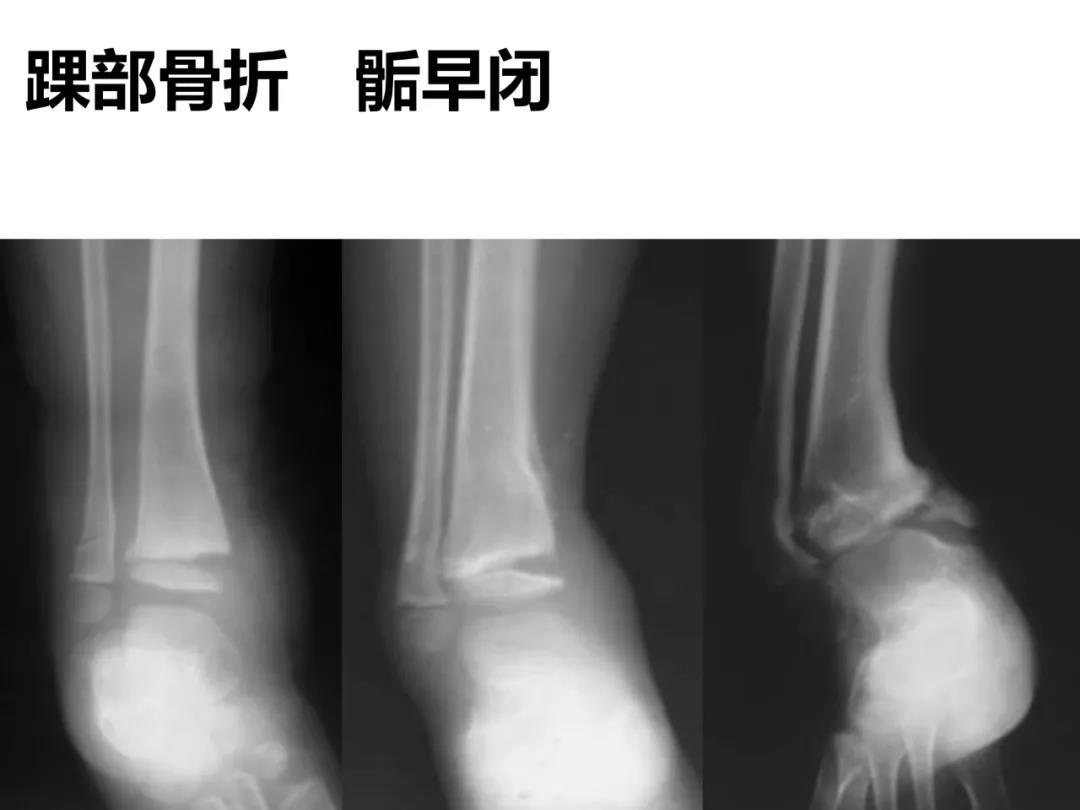

小儿骨科X线片汇总,临床读片宝典!